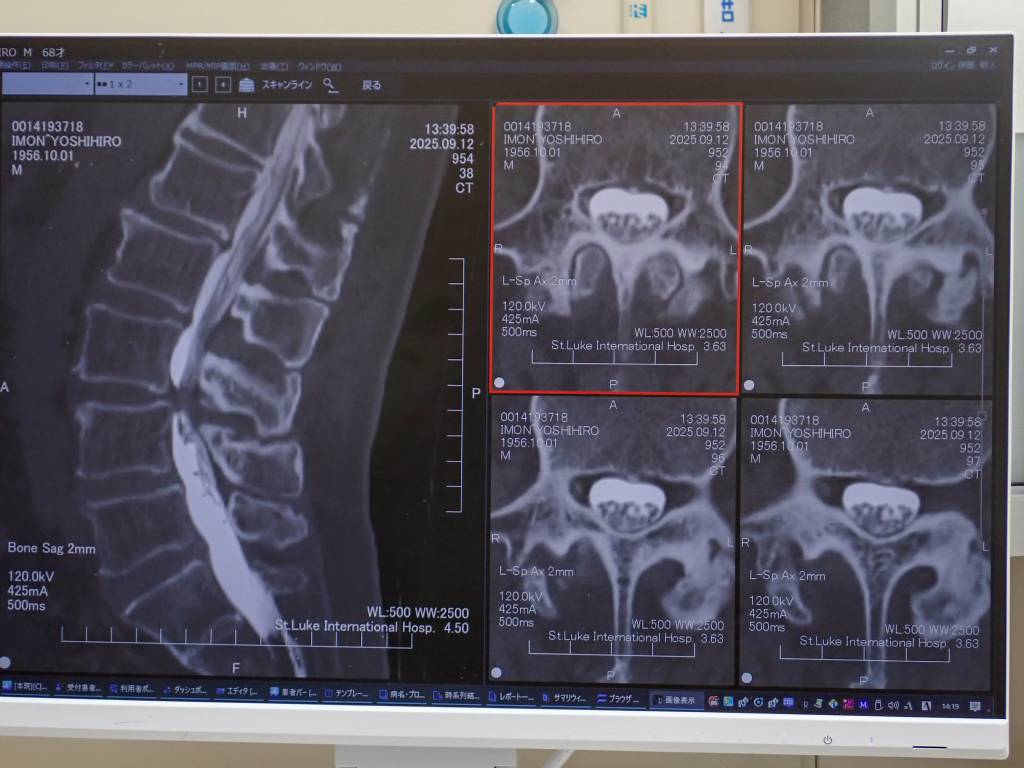

CTスキャン画像。

緑色が造影剤。

少し心配した3年前の首の手術の経過は上々でした。